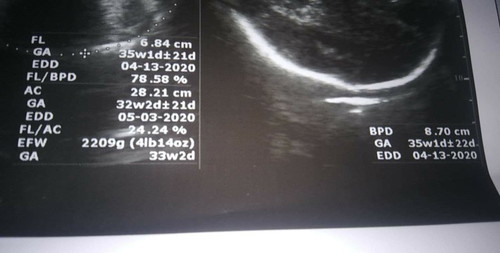

Mga momsh, ano po dapat sundin dito sa Ultrasound. Kasi sabi April 13 EDD ko, tas sa baba left side naman biglang May 3. Im currently 38 weeks at di ko alam kung ano talaga due date ko ☹️

+- po kc yan madam. Basta po 37weeks up to 41weeks. Pg 40weeks na po close monitor n kau ni OB